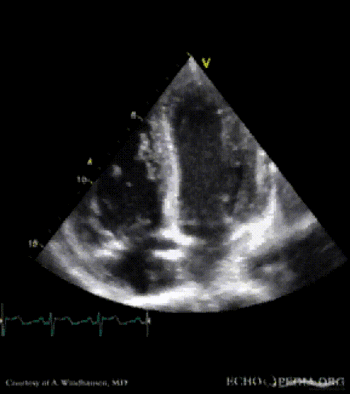

Severe Hypertrophic Cardiomyopathy (HCM)

Case description: Severe Hypertrophic Cardiomyopathy (HCM)

Courtesy of: A. Windhausen, AMC, The Netherlands

MM0007.gif MM0009.gif